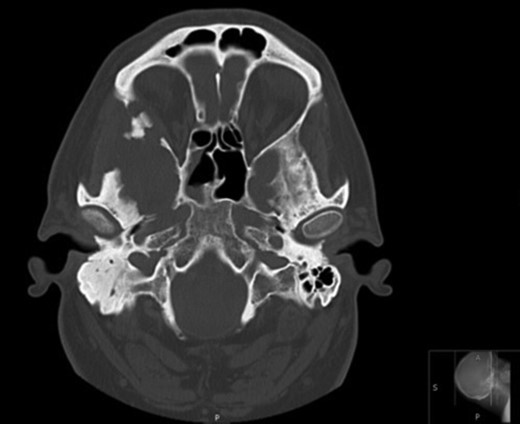

Axial CT images demonstrating bony involvement of the right mastoid and greater wing of the sphenoid.

Langerhans cell histiocytosis (LCH) is a rare histiocytic disorder of unpredictable clinical course and varied modes of presentation. The spectrum of presentation is wide, ranging from isolated eosinophilic granulomas to multiple lesions and diffuse systemic involvement. We present the case of a 52-year-old man, who presented with an 8-week history of worsening otalgia and superficial temporal tenderness attributed to otitis externa within the community and subsequently giant cell arteritis. Computed tomography and magnetic resonance imaging were undertaken due to atypical features, which demonstrated bony destruction within the right greater wing of the sphenoid, squamous part of temporal and mastoid bone, with middle cranial fossa communication. Intra-orbital extension was noted with abutment of the lateral rectus muscle. Mastoid biopsies demonstrated a mixture of lymphocytes, eosinophils and monomorphic epithelial cells with pale cytoplasm and focal areas of granulation tissue/necrosis. The features were consistent with a diagnosis of LCH, and the patient was subsequently transferred to a tertiary centre for definitive treatment.